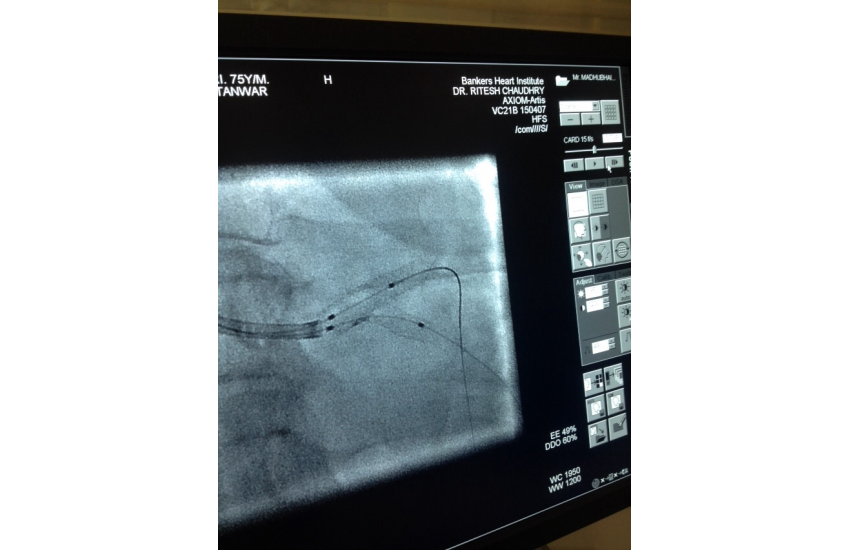

75 years old male presented with unstable angina undergone CAG which is shown LMCA bifurcation lesion first option given for CABG surgery but Pt. is not willing for that so after discussing all the risk of LMCA bifurcation kissing steanting Than patient and relatives ready for that and with all life support system successfully done by Dr N T sir. After steanting patient is doing well.